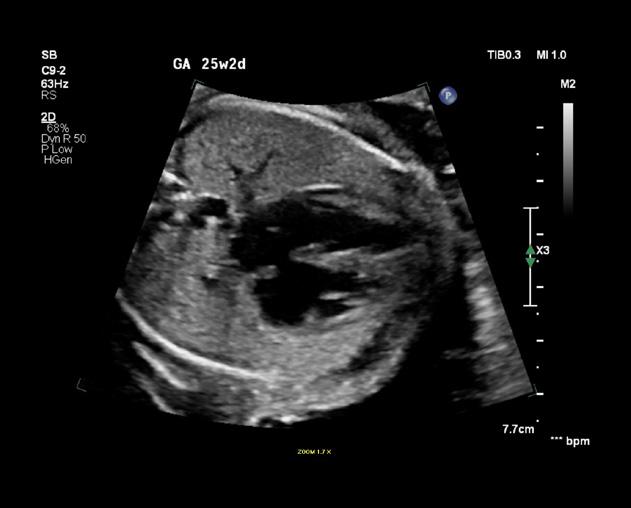

La tétralogie de Fallot est la plus fréquente des cardiopathies congénitales cyanogènes, représentant près de 8 % d’entre elles. Cette malformation tire son nom d’Étienne-Louis Arthur Fallot, qui l’a décrite en 1888.

La tétralogie de Fallot se caractérise par quatre anomalies distinctes, comme ÉtienneLouis Fallot, anatomopathologiste, les avait observées lors d’autopsies. En réalité, deux de ces anomalies suffisent à expliquer la physiopathologie de cette malformation, les deux autres n’étant que des conséquences. Cette introduction vise à offrir un aperçu des caractéristiques cliniques, des défis diagnostiques et des approches thérapeutiques actuelles de cette pathologie (figure 1 ).

Anomalies anatomiques de la tétralogie de Fallot :

■ Rétrécissement de l’artère pulmonaire.

■ Hypertrophie du ventricule droit, qui compense la pression exercée par le rétrécissement de l’artère pulmonaire.

■ Communication interventriculaire entre les ventricules droit et gauche.

■ Malposition de l’aorte à droite, chevauchant le septum interventriculaire. Ce déplacement partiel au-dessus du ventricule droit résulte du défaut d’alignement à l’origine de la communication interventriculaire.

Cœur normal Tétralogie de Fallot

Dextroposition de l’aorte Sténose pulmonaire

Communication inter-ventriculaire

Hypertrophie ventriculaire droite

Figure 1 : Différence entre un cœur normal et un cœur ayant une malformation appelé la tétralogie de Fallot.

Anomalies principales :

■ Sténose (rétrécissement) de la voie d’éjection du ventricule droit : Cette sténose peut se situer au niveau de l’infundibulum pulmonaire, de l’anneau pulmonaire ou du tronc de l’artère pulmonaire (avant la bifurcation en deux artères pulmonaires). Le rétrécissement peut être localisé ou prédominer sur une de ces trois parties dans les formes mineures. En revanche, dans les formes sévères, il peut s’étendre à l’artère pulmonaire, y compris aux branches droite ou gauche.

■ Communication interventriculaire (CIV) : Cette communication se situe près de l’origine des gros vaisseaux, notamment de l’aorte. Elle résulte d’un mauvais alignement entre l’aorte et la portion musculaire du septum interventriculaire.

Ces caractéristiques anatomiques et physiopathologiques permettent de comprendre la complexité et la gravité de la tétralogie de Fallot, nécessitant une prise en charge médicale spécialisée.